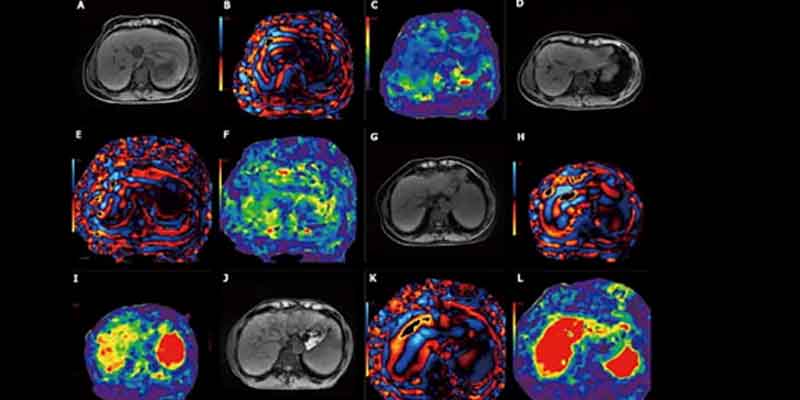

A diferencia de una resonancia magnética abdominal completa, que captura una amplia gama de estructuras abdominales y suele requerir el uso de medio de contraste, el hepatograma MASLD se enfoca únicamente en el contenido de grasa y la rigidez del hígado. Para ello, se apoya en dos técnicas clave: la cuantificación de grasa por resonancia magnética y la elastografía por resonancia magnética, que utiliza ondas mecánicas suaves para medir la rigidez hepática, un indicador directo de fibrosis.

“Es, esencialmente, un examen diseñado a la medida. Lo redujimos a las secuencias esenciales que responden a una pregunta muy específica: ¿este paciente padece o no fibrosis hepática esteatósica?”, comentó el doctor Nakul Gupta, radiólogo diagnóstico en el Hospital Houston Methodist, quien desarrolló el nuevo protocolo junto al doctor Victor.

Foto: Flow